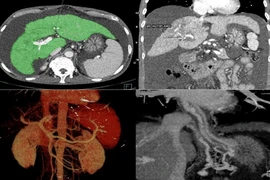

(khoahocdoisong.vn) - Lần đầu tiên tại Việt Nam, Bệnh viện Đa khoa Phú Thọ đã ứng dụng can thiệp TIPS điều trị xơ gan cổ trướng cho bệnh nhân tràn dịch ổ bụng mức độ nhiều, đã từng bị chảy máu tiêu hóa 3 lần.